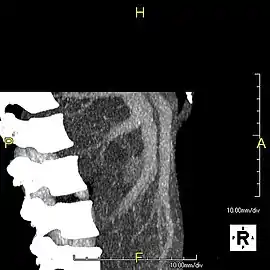

Left lobe liver tumor

The liver is a vital organ and supports almost every other organ in the body. Because of its strategic location and multidimensional functions, the liver is prone to many diseases.[51] The bare area of the liver is a site that is vulnerable to the passing of infection from the abdominal cavity to the thoracic cavity. Liver diseases may be diagnosed by liver function tests–blood tests that can identify various markers. For example, acute-phase reactants are produced by the liver in response to injury or inflammation.